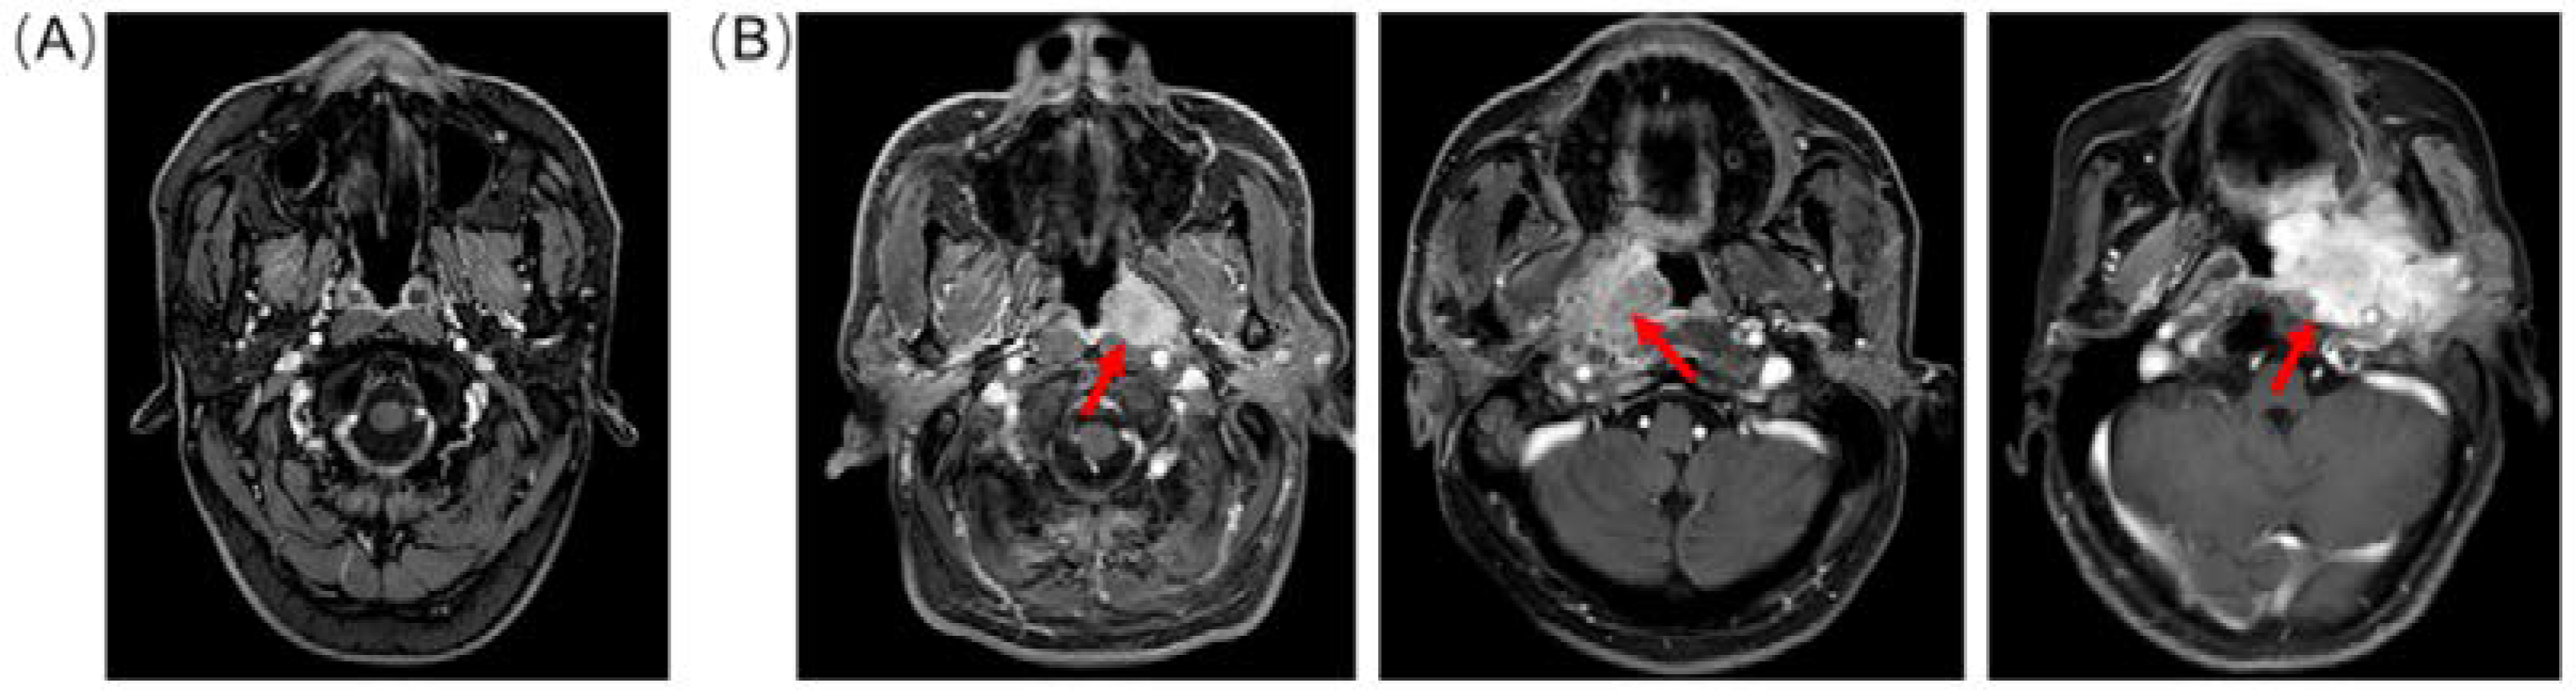

- Wong, L.M.; King, A.D.; Ai, Q.Y.H.; Lam, W.K.J.; Poon, D.M.C.; Ma, B.B.Y.; Chan, K.C.A.; Mo, F.K.F. Convolutional neural network for discriminating nasopharyngeal carcinoma and benign hyperplasia on MRI. Eur. Radiol. 2021, 31, 3856–3863. [Google Scholar] [CrossRef]